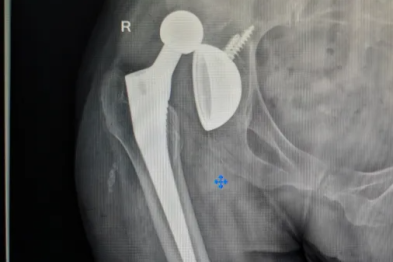

老人摔出「人生大坎」,多学科联手成功置换肩关节